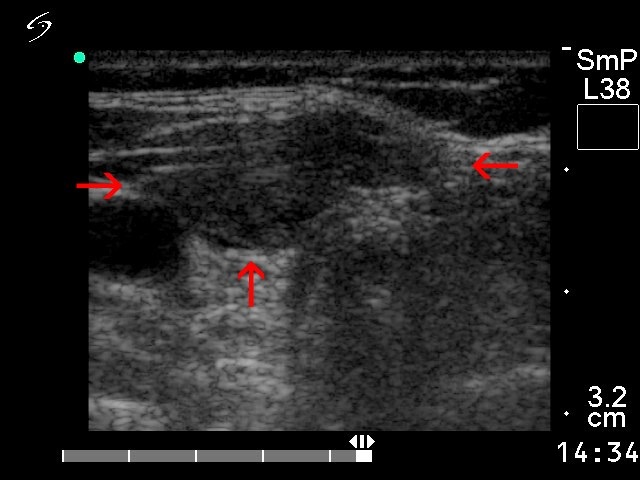

Anaplastic carcinoma - Figure 2. Ultrasound properties.

Most if not all anaplastic carcinomas occur in hypoechogenic nodules which comprises almost the entire affected lobe; only a thin normal parenchyma can be detected (marked with green arrows). Intranodular necrosis (marked with red arrows) is a frequent finding.

Direct spread of the tumor is a rare finding in thyroid carcinomas other than anaplastic cancer. In this case macroscopic pathology disclosed that the ventral smaller hypoechogenic area marked with red arrows corresponded to direct extracapsular spread of the tumor.